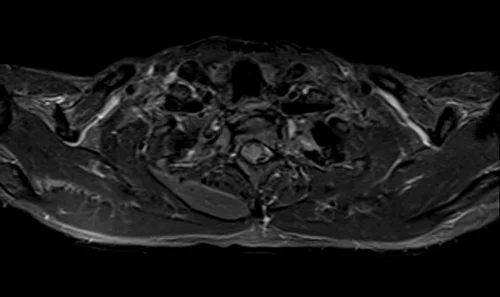

MRI brachial plexus axial STIR images